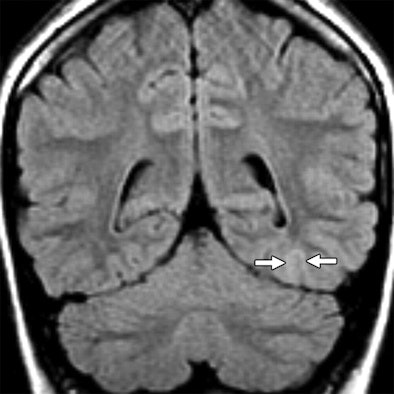

| Seventeen-year-old girl with intractable nocturnal seizures since the age of two. Above, coronal fluid-attenuated inversion recovery (FLAIR) 1.5-tesla MR image showing questionable curvilinear focus of juxtacortical high signal intensity (arrows) in left occipital lobe. Abnormal signal intensity was missed at first review of images. Below, coronal FLAIR 3-tesla MR image showing curvilinear band of high signal intensity (arrows) in left occipital juxtacortical white matter without apparent mass effect. Focus was surgically resected and histologic finding was focal cortical dysplasia with balloon cell features. |

| Images courtesy of the American Journal of Roentgenology and Oregon Health & Science University; from Phal P, Usmanov A, Nesbit G, et al. Qualitative comparison of 3-T and 1.5-T MRI in the evaluation of epilepsy. AJR. 2008;191:890-895. Figure 1. |